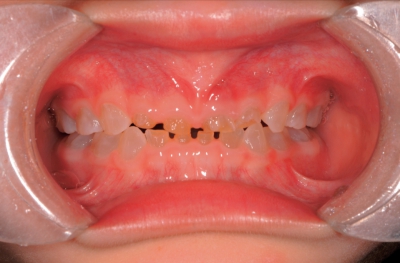

3歳5か月の男児。歯の色の異常を主訴として来院した。色調は萌出時から変化していないという。初診時の口腔内写真を別に示す。

骨形成不全症に伴う歯科疾患。1型コラーゲンの異常による疾患。

乳歯・永久歯ともに歯の着色、エナメル質を介して形成不全の象牙質(琥珀色、オパール様)を認める。